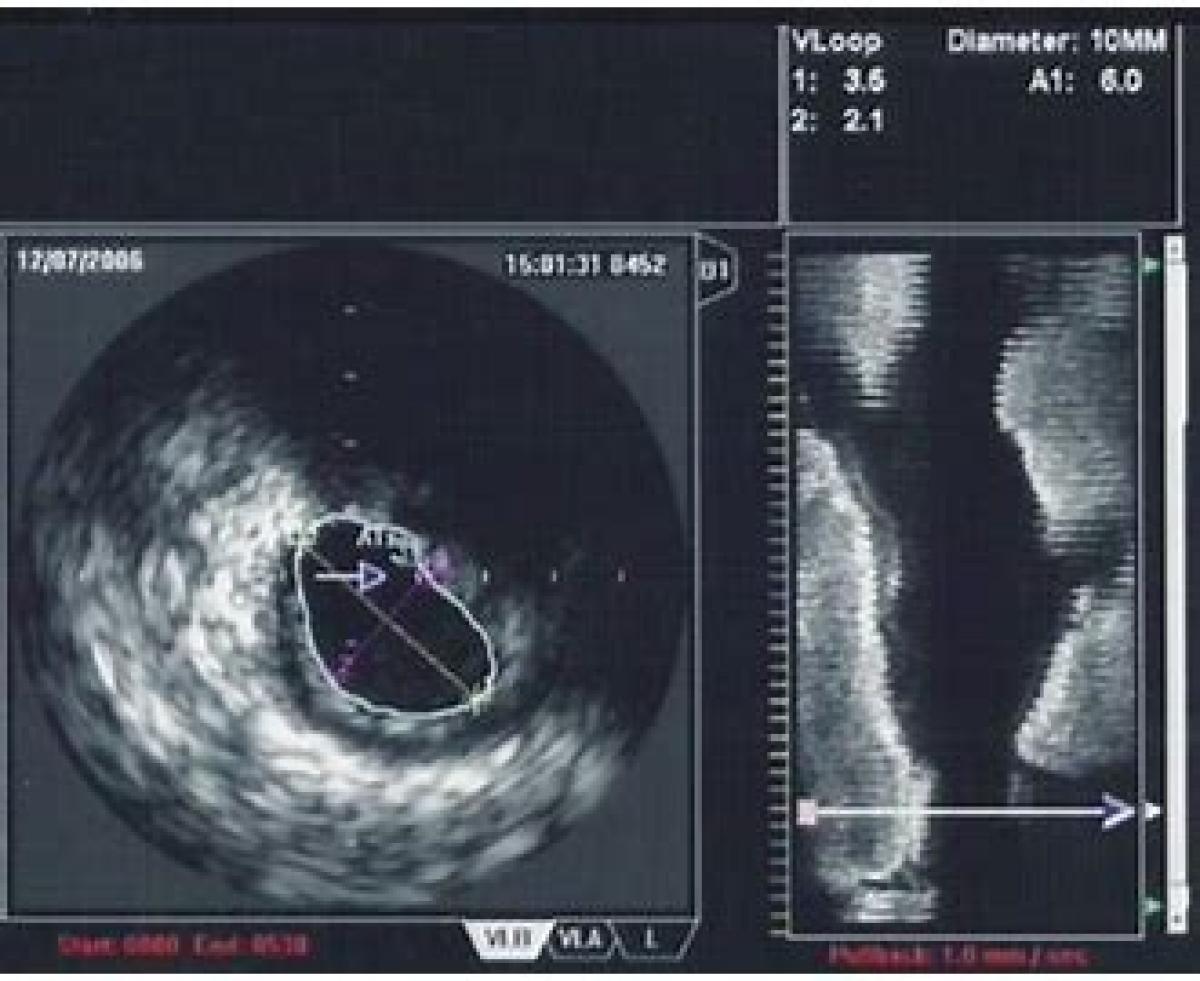

با رشد روزافزون تکنولوژی در تشخیص و پایش بیماری های قلبی عروقی نیاز به استفاده از سیستم اولتراسوند داخل عروقی (IVUS) به عنوان راهکاری عملی با دقت و صحت بسیار بالا در تشخیص بیماری ها به امری واضح تبدیل شده است.

طی مطالعات و تحقیقات انجام شده در چندین مقاله و به جهت بررسی و تحلیل سیستم IVUS در مقایسه با دستگاه آنژیوگرافی به تنهایی، که در دو مرحله اصلی ارزیابی اثربخشی و هزینه یابی انجام می شود، شواهد موجود با استفاده از روش متاآنالیز مورد سنتز قرار گرفت و رتبه اثر بخشی هر تکنولوژی با کمک روش های تصمیم گیری چند شاخصه ساو، تاپسیس، ویکور و تئوری خاکستری تعیین شد. نتیجه این سنتز اثر بخشی بهتر سیستم IVUS را در مقایسه با دستگاه آنژیوگرافی به تنهایی نشان داد. در مرحله هزینه یابی نیز، میزان هزینه های احتمالی تحمیل شده بر جامعه در صورت بکارگیری سیستم IVUS در کنار دستگاه آنژیوگرافی گویای هزینه اثر بخشی سیستم IVUS در برابر فقط دستگاه آنژیوگرافی به تنهایی را نشان می دهد.